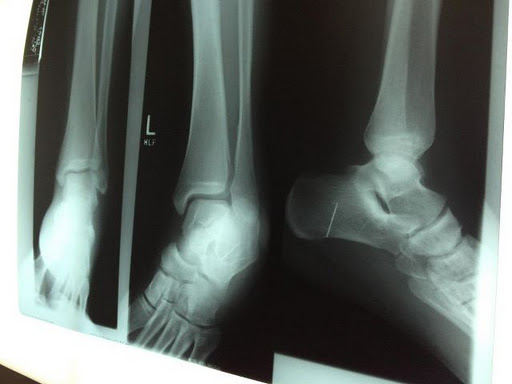

Many of us have weird corpus alienum stories. Take, for example my cousin’s husband who fell a few days ago. Concerned, Ben went to the doctor and got an x-ray. Ben learned three things that day.

and 3. (prepare yourselves, friends)…Ben has a sewing needle in his foot.

Apparently when Ben was a kid, he must have stepped on a sewing needle. It has been living in his heel peacefully for 20+ years.